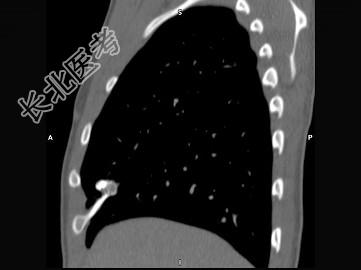

- 单项选择题男,16岁, 咳嗽十余年,结合图像, 最可能的诊断是 ( )

A、胸廓内骨软骨瘤

B、周围型肺癌

C、陈旧性肺结核

D、胸膜粘连

E、以上都不是